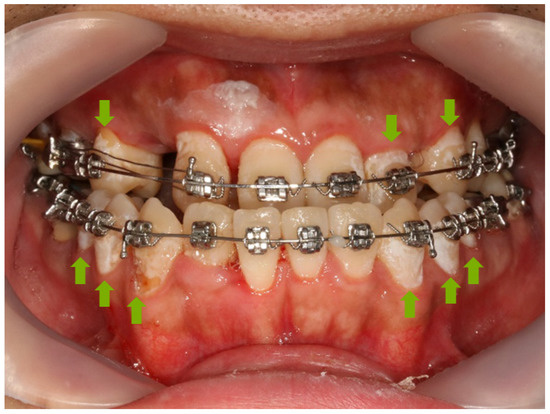

3.8. Anti-demineralization